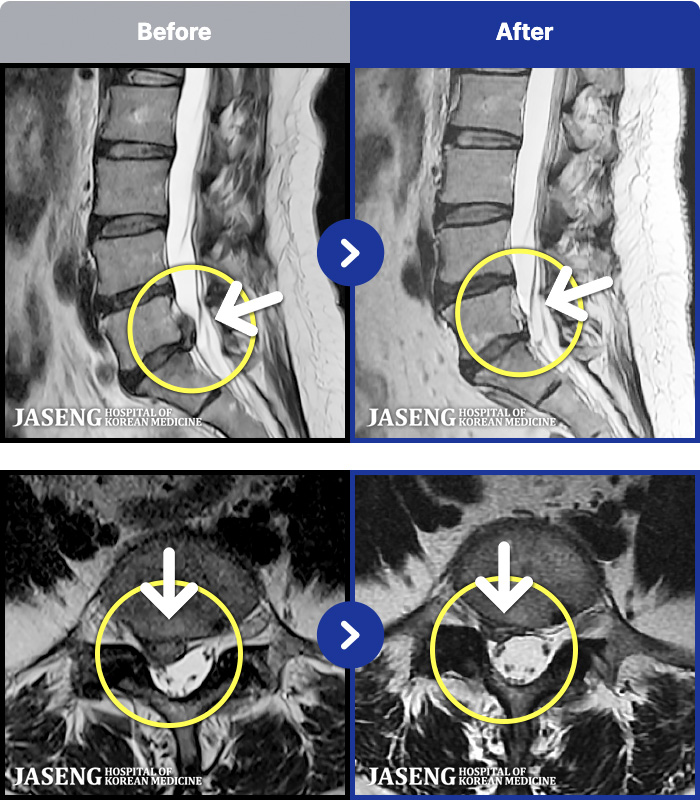

MRI ġ

101 MRI ũ ʸ Ȯϼ.

[Կñ:24.03.21~24.09.23]

[õ_㸮ũ] Ǫ ݺ ؽ Ͽ

No.101

ȸ 28,211

2025.01.03